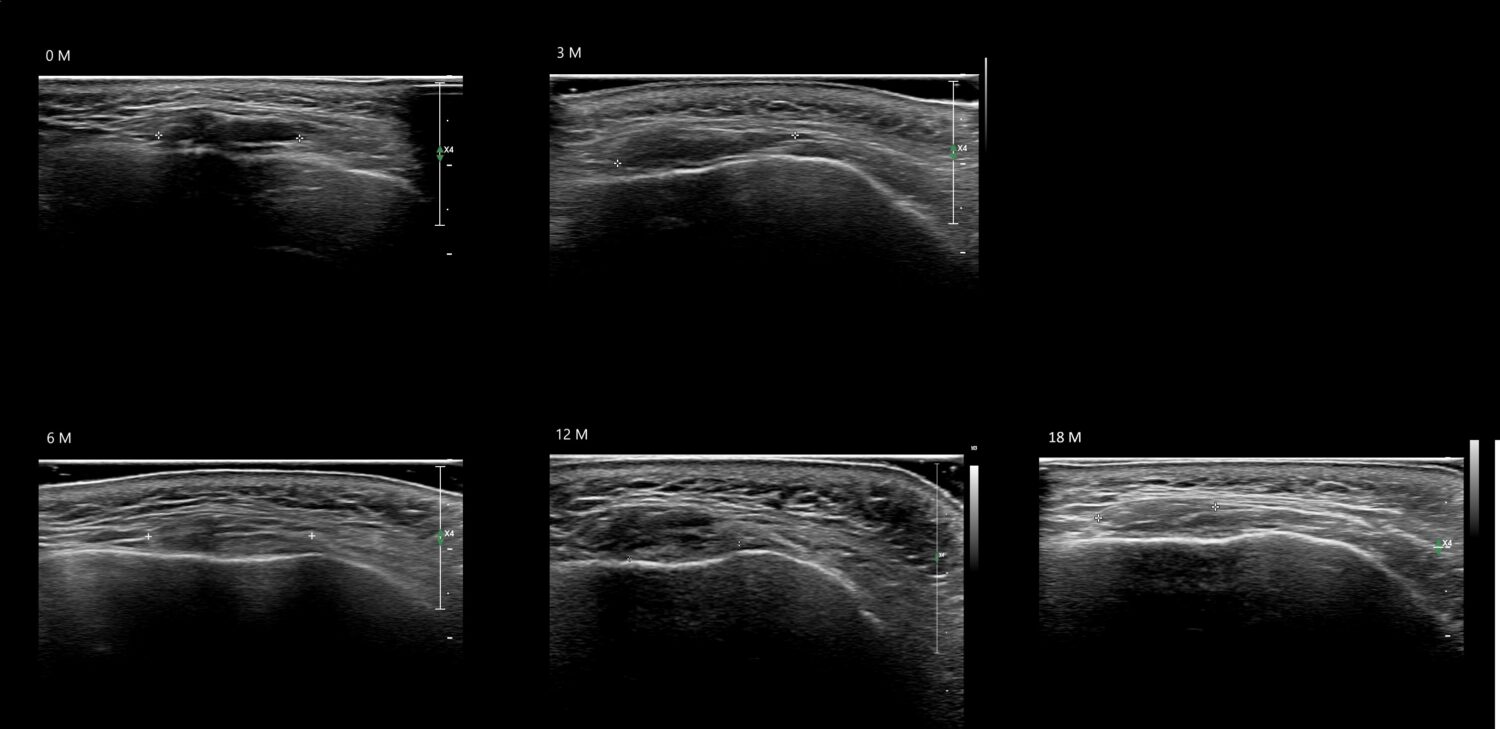

Draw in the image on the right where the fillers are located. To check if your answer is correct, please click on the secondary image.

Draw in the second image below where the fillers are located. To check if your answer is correct, swipe the first image to the right.